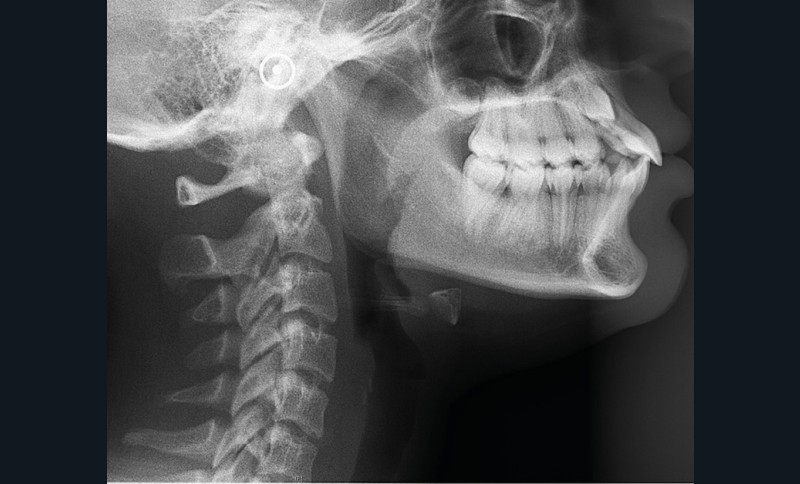

Les examens cliniques et radiologiques ont mis en évidence l’inclusion de 13 et 23, une légère classe II bilatérale par perte d’ancrage, un biotype parodontal de type IV de Maynard et Wilson avec une insertion du frein mandibulaire antérieur papillaire, une biproalvéolie et une typologie hypodivergente. La réalisation d’un examen tridimensionnel a permis de confirmer la localisation palatine de 23 et vestibulaire de 13 ainsi que de visualiser l’étendue des résorptions radiculaires touchant 12, 21 et 22 (fig. 1a-i).

Un appareil multi-attaches .022 x .028 (prescription de Roth) est posé sur toute l’arcade mandibulaire et sur les secteurs postérieurs maxillaires (17 à 14 et 27 à 24) afin d’éviter au maximum la sollicitation de 11 et 21 et donc de limiter les résorptions radiculaires.

Les résorptions radiculaires des dents adjacentes aux canines maxillaires incluses sont en effet fréquentes avec un risque plus important chez les femmes. La localisation sagittale de la canine incluse constitue un facteur de risque dans la présence de résorptions radiculaires [3]. Le recours aux examens tridimensionnels est donc indispensable dans le traitement de ces cas.